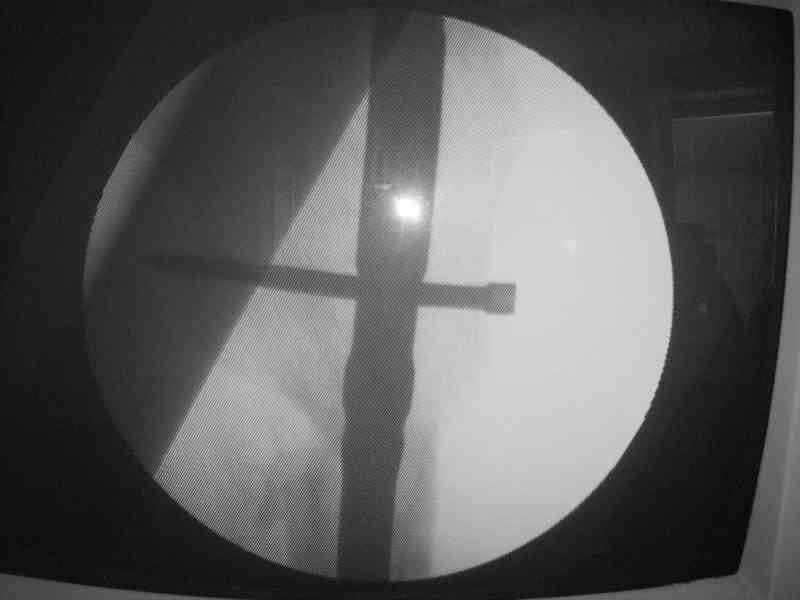

Могу скромно напомнить о существовании стержня нашей модификации.

В частности, на проксимальном конце сделано еще одно дополнительное статическое отверстие. Можно ввести в проксимальном отделе 4 винта, из них 3 статические (2 в круглые отверстия и 1 по нижнему краю овального). Картинки в приложении. На дистальном конце стержня тоже кое-что улучшено. Спрашивайте в аптеках, как говорится. Выпускается предприятием "ЦИТО" (Москва), то есть это малобюджетное решение.